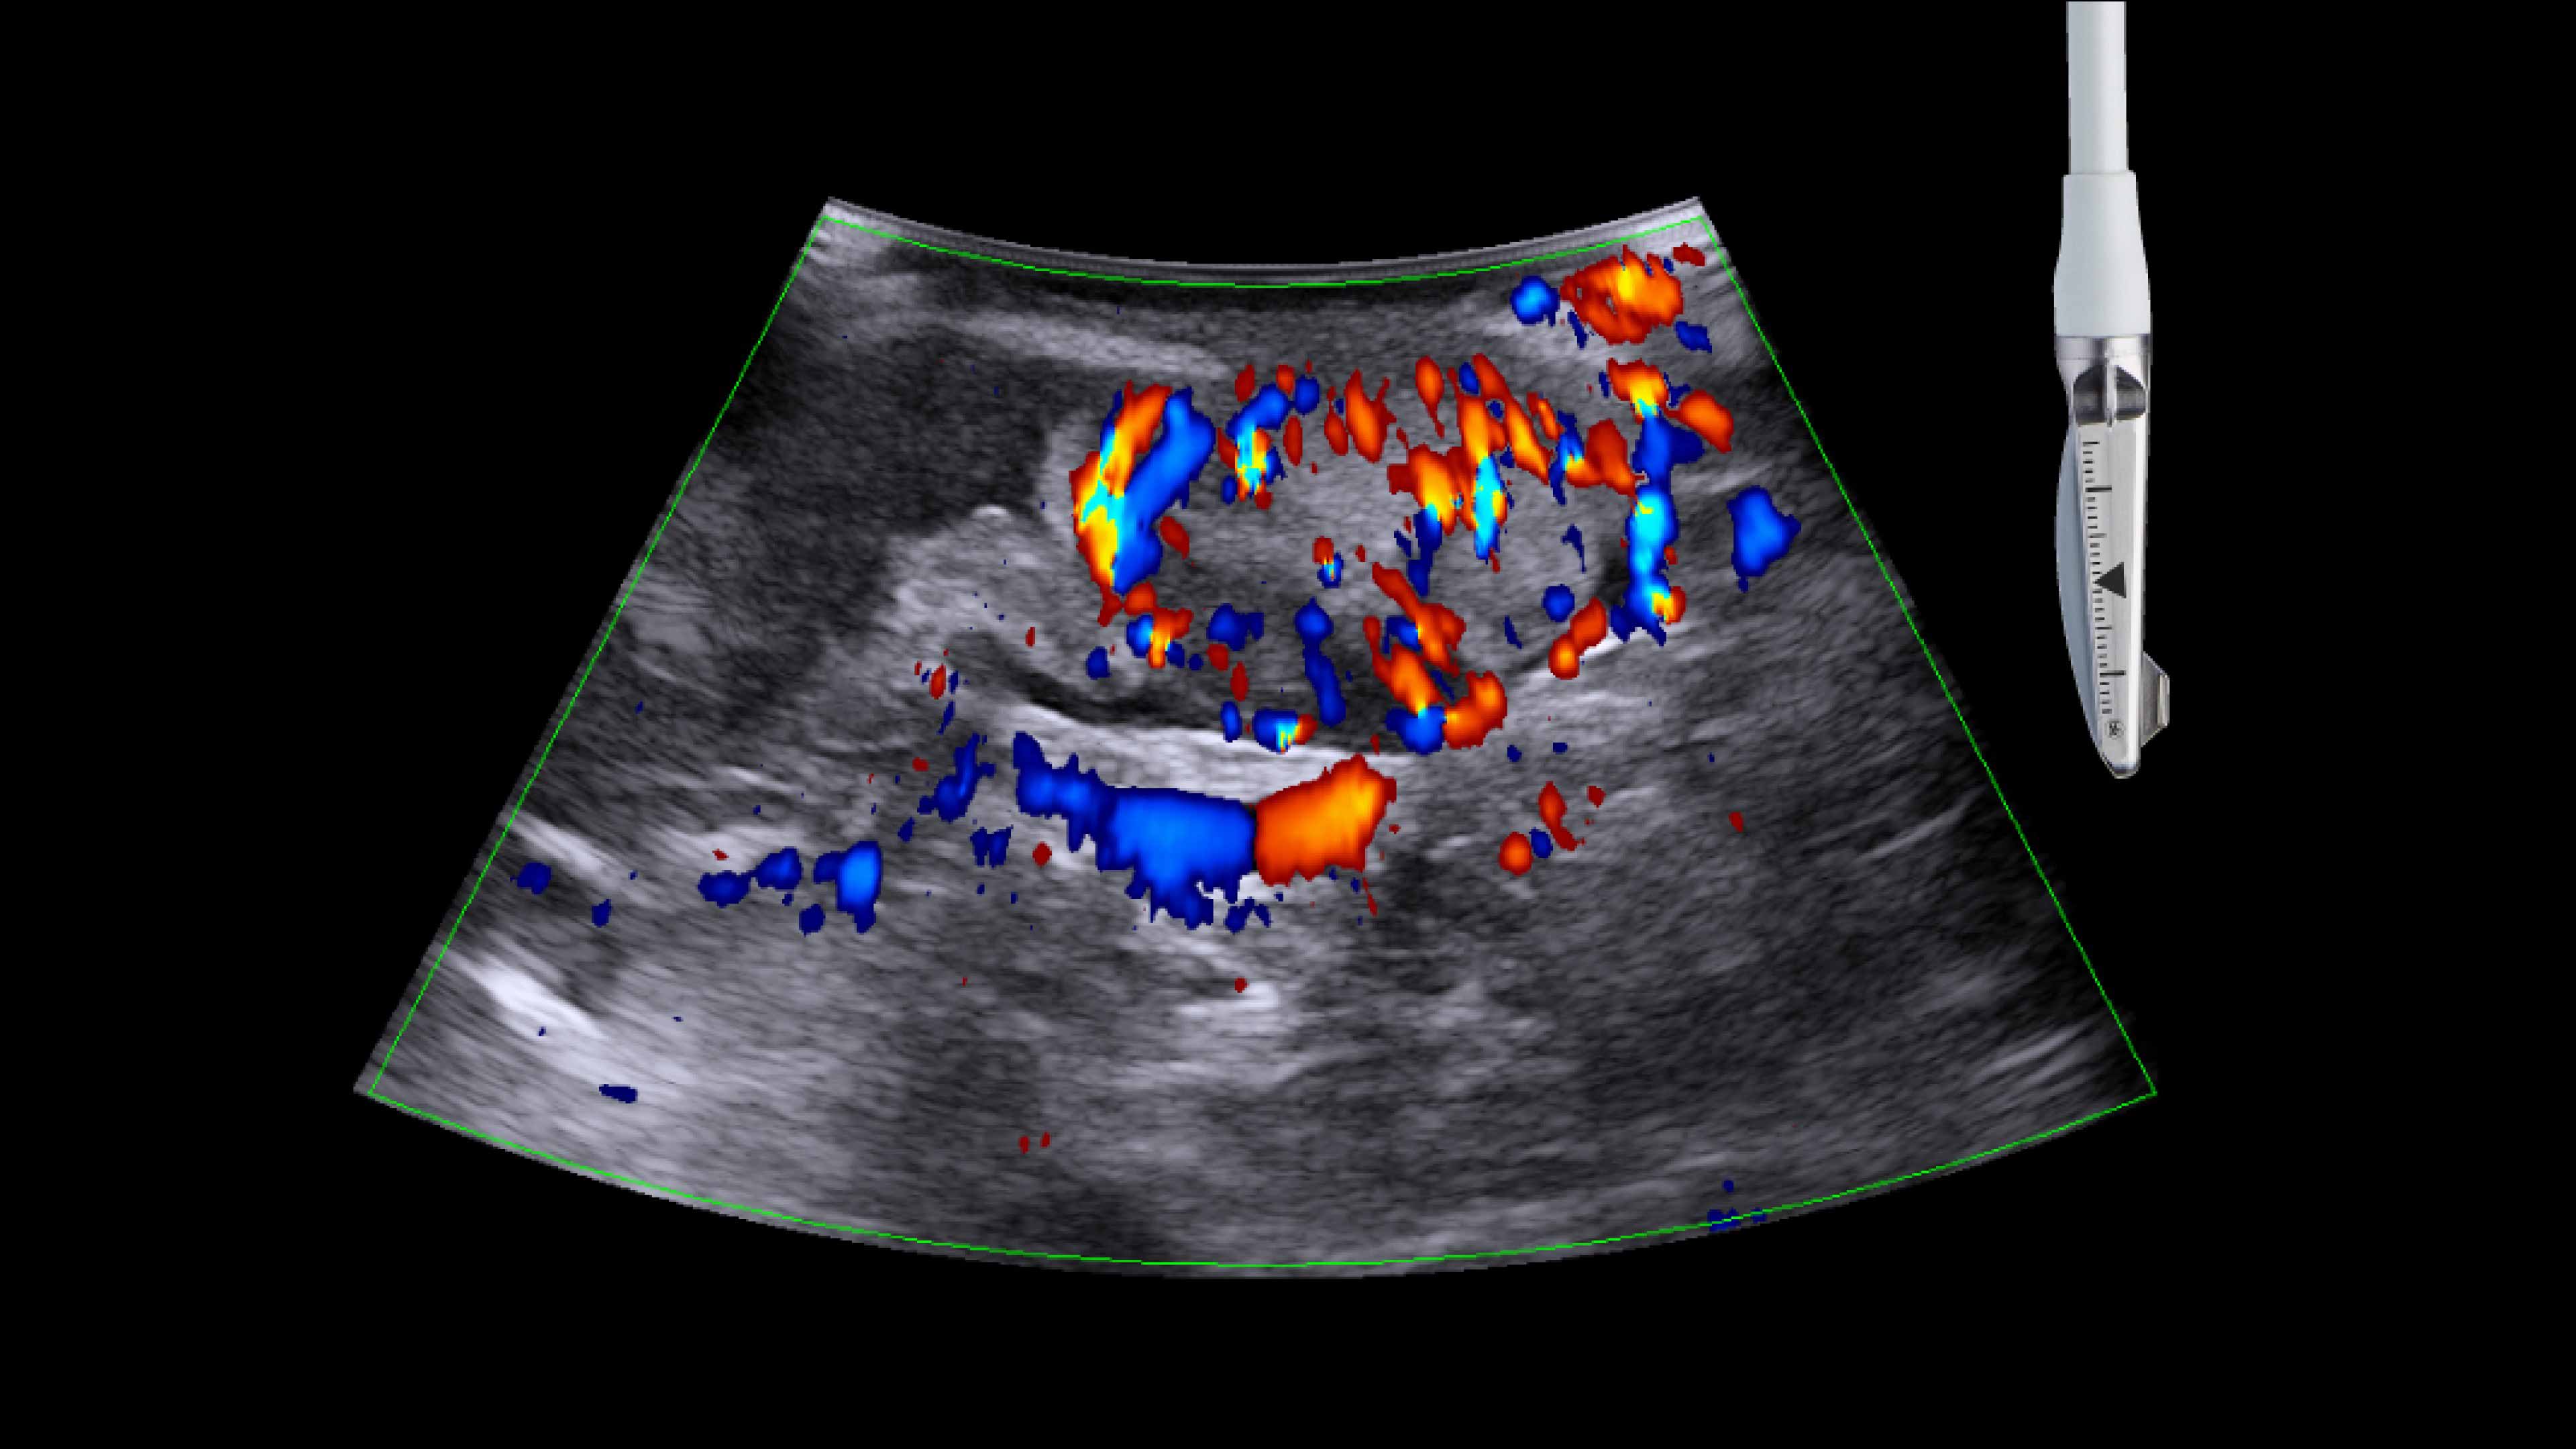

Cholecystectomy ultrasound

Active imaging with real-time intraoperative ultrasound supports fast imaging of the biliary system and is non-radiating, helping you reduce radiation hazards to your patients and staff.

Imaging to guide cholecystectomies

Discover the clinical benefits of active imaging with intraoperative ultrasound for laparoscopic cholecystectomy procedures. Using bkActiv and the Advanced Laparoscopic Transducer, surgeons can visualize anatomy and monitor progress as many times as needed during the procedure.

The value of iUS in cholecystectomies

iUS is beneficial for cholecystectomies due to its safety, quick and repeatable imaging capabilities and ability to detect choledocholithiasis and enable visualization of biliary tract anatomy.

• iUS has minimal safety risks as it is non-irradiating and does not required cannulation. ¹⁻³

• iUS can be used dynamically throughout dissection adding minimal time to a cholecystectomy procedure. iUS can also repeated, helping to assess common bile duct integrity at the end of the procedure.¹⁻⁵

• iUS helps differentiate between sludge, stone, polyps, cysts, and tumors when determining if there is a presence of gallstones in the common bile duct.⁵,⁶

• iUS uses color flow doppler to help differentiate between vessels and ducts and is overall effective at imaging difficult cases such as inflammation or fibrosis .¹,⁴⁻⁶